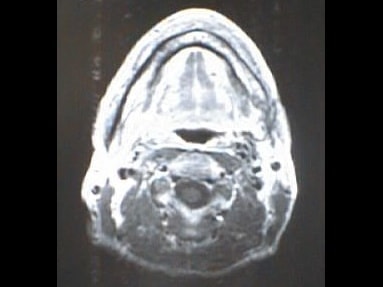

MRI画像比較

入院当時MRI画像①

入院3か月後癌消滅MRI画像①